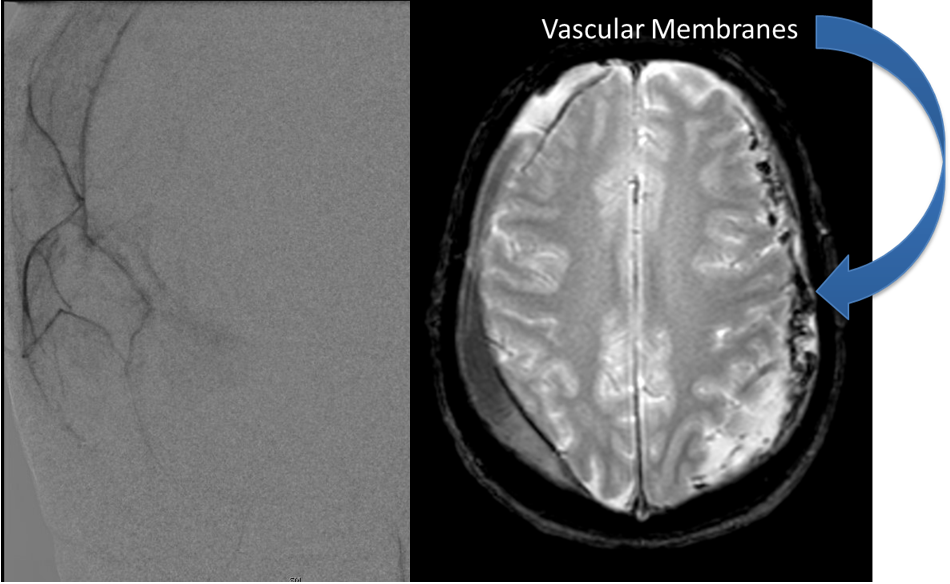

Brain:

Atypical Convexity Meningioma

Author: Jonathan L. Brisman M.D., F.A.C.S., Read More!